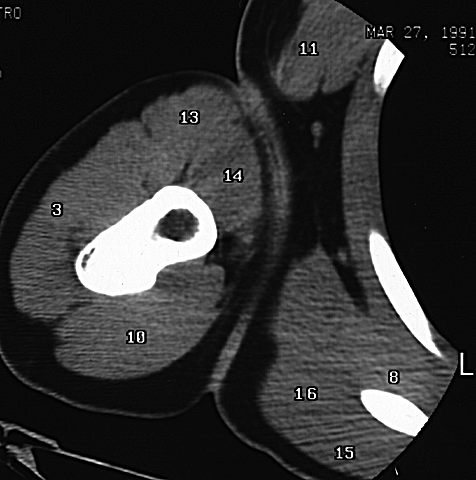

Shoulder CT 5

3. Deltoid m.

8. Subscapularis m.

10. Triceps m.

11. Pectoralis major m.

13. Biceps M. - long head

14. Biceps m. - short head

15. Teres major m.

16. Latissimus dorsi m.